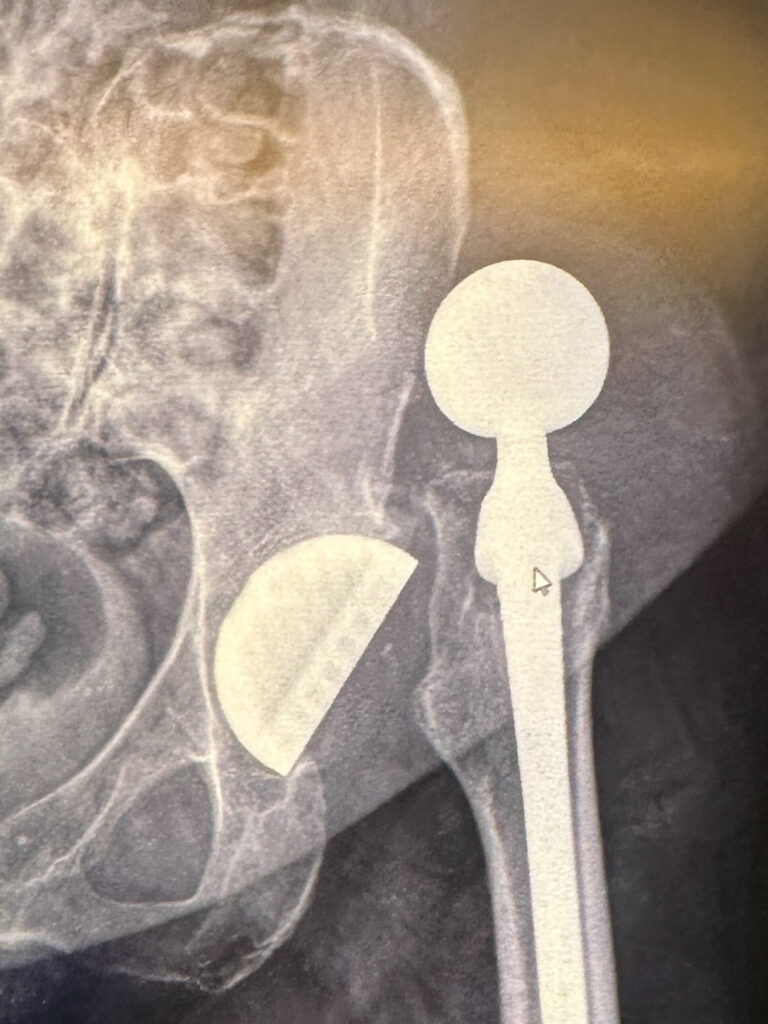

Her hip dislocated violently and without warning. She was in excruciating pain and unable to move. An ambulance took her to emergency, where her hip was put back into place. It was traumatic, frightening, and overwhelming to witness. The feeling of being helpless can be difficult to bear.

During this process, a tendon was torn – something we didn’t know at the time. In the weeks that followed, she couldn’t bear weight on her leg or walk properly. She kept saying something wasn’t right. Imaging later confirmed a full tendon tear with retraction.

When a hip replacement dislocates

What we learned next mattered deeply: there is a short window to repair this kind of injury before it becomes far more difficult, with worse outcomes. Her surgeon (amazing human) acted quickly, and she received the repair she needed.

Hip dislocation is rare, and in my mom’s case, it was an emergency. The pain was immediate and intense. If someone experiences sudden, severe pain, an inability to move, or visible joint deformity, this should always be treated as a medical emergency – call for help right away.